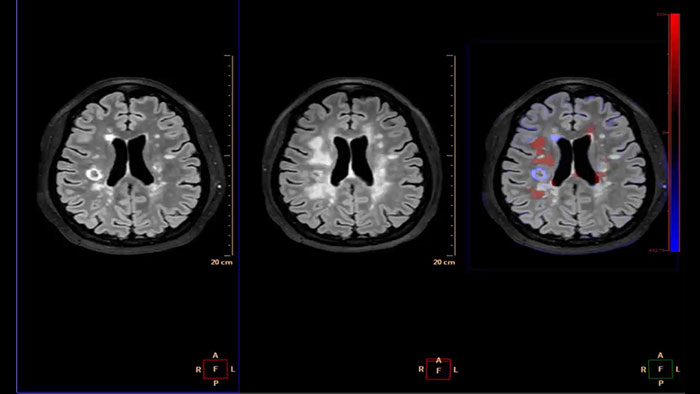

Longitudinal Brain Imaging (LoBI)

MR Longitudinal Brain Imaging (LoBI)

Gain an optimized view of the body’s most complex organ

Supports the visualization of brain images for the evaluation and monitoring of changes across multiple time points. The application performs automatic registration between studies and provides semi-automatic segmentation and editing tools for volumetric measurement of brain lesions.

Benefits

• The Comparative Brain Imaging feature uses bias field-correction, intensity scaling, image registration and mathematical subtraction to provide color-coded images highlighting subtle brain changes over time.